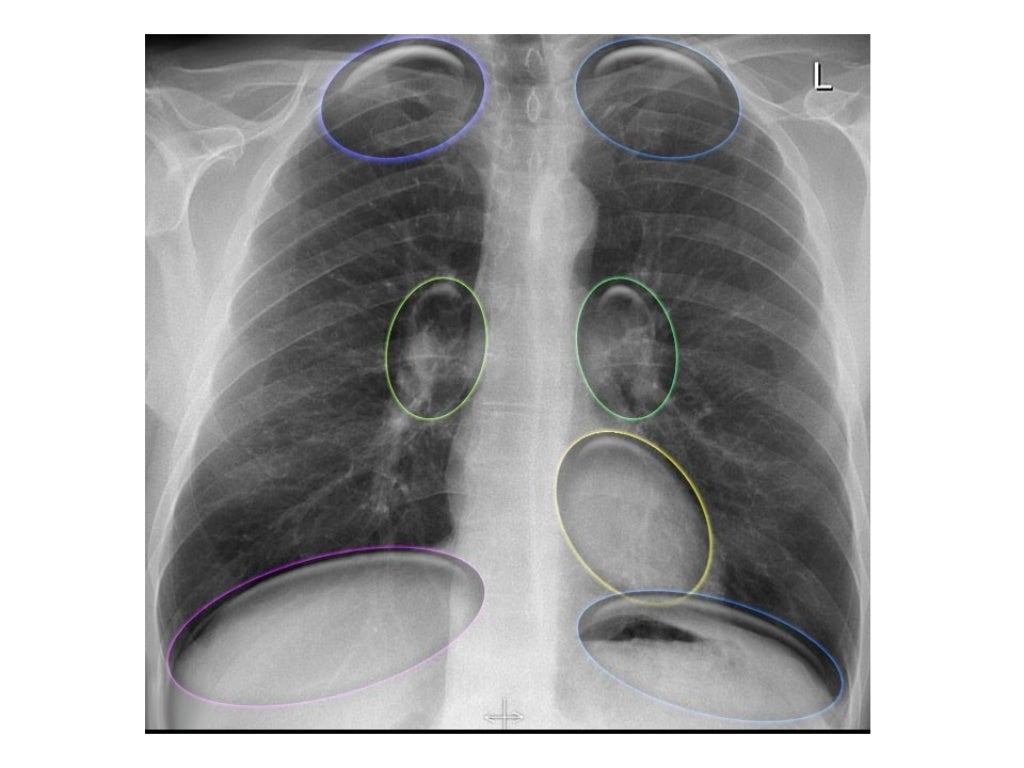

Chest Xrays Basic Interpretation

Diagnostics Free FullText Longitudinal Chest Xray Scores and What Does Indication Mean On An X Ray Report for instance, you have pain in your foot and an mri shows several possible reasons for the pain. what does indication mean on a radiology report? A radiology report is the radiologist’s written findings of what they saw on your medical imaging and concludes with what they think is going on. It provides information about why the patient. What Does Indication Mean On An X Ray Report.